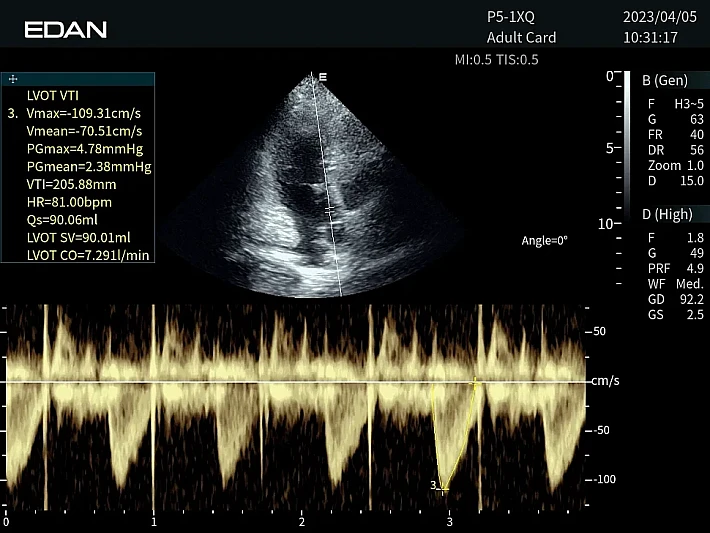

Медицинское оборудование и сервисное обслуживание